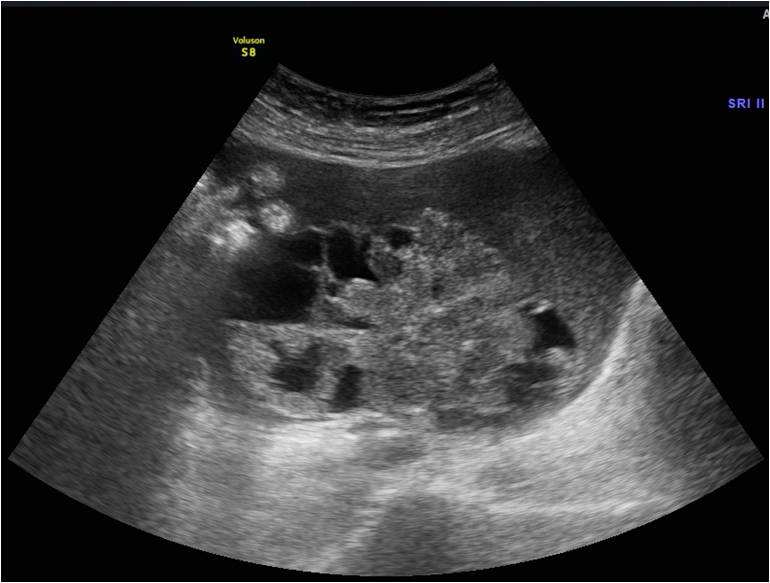

子宫内膜癌,已经病理证实

子宫内膜癌,子宫粘膜下肌瘤b超表现

双侧卵巢癌